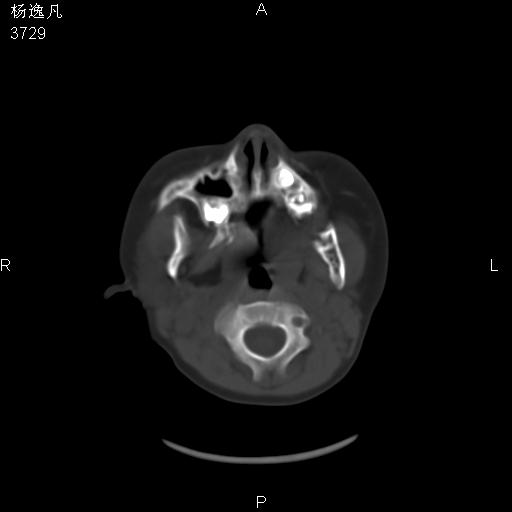

男性,5岁,面部受外伤,余无特殊

薄层

鼻咽顶后变窄。顶后壁增厚,考虑腺样体肥大。其它未异常/

头颅ct平扫未见明确外伤性征象,右侧面部及颞部软组织肿胀,后鼻腔软组织影增大,增厚,鼻咽顶部变窄,考虑鼻咽腺样体增值肥厚。